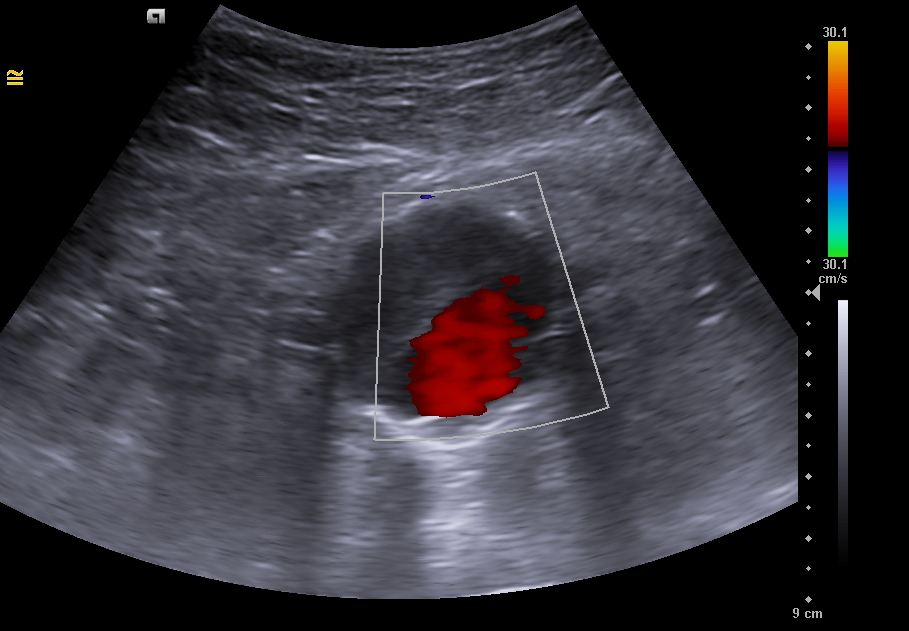

En la ecografía clínica se observa la aorta abdominal con calibre aumentado de tamaño (46 x 41 mm de diámetro), trombo mural interior y luz del vaso de 20 x 27 mm compatible con aneurisma de aorta abdominal fusiforme que se extiende hasta bifurcación aortoilíaca. Arterias ilíacas comunes sin datos de afectación.